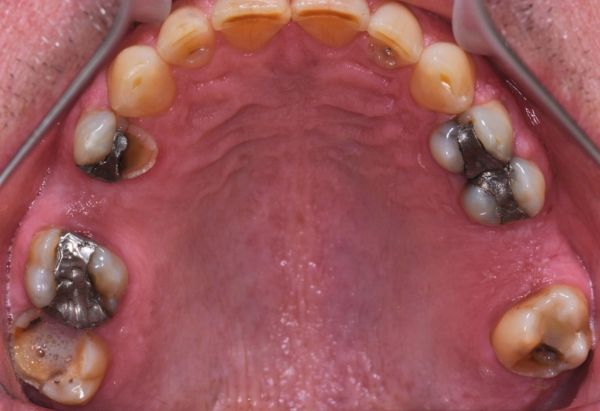

Before

Bonded Amalgams